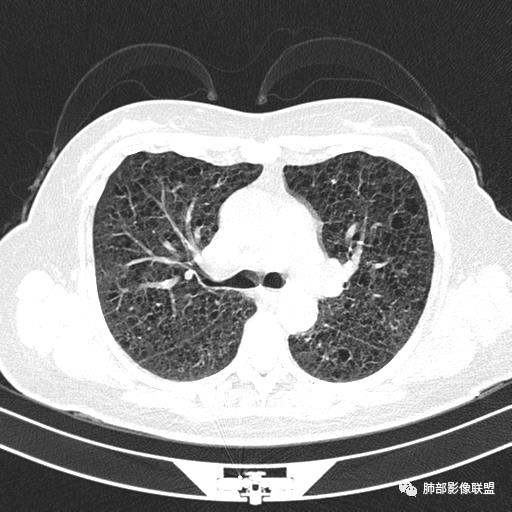

双肺弥漫囊腔,累及肋膈角,囊腔形态相对规则单一。

CT平扫示双肺弥漫分布大小不等囊状薄壁透光区,无内、中、外带分布差异,间质稍示增厚。拟LAM

中年育龄期女性,双肺多发含气囊腔弥漫性分布,囊间肺组织结构正常,常规考虑Lam

双肺多发大小相近的囊状影,分布趋势趋于一致,中年女性,考虑LAM。部分囊内见血管及分隔影,小叶中心性肺气肿代排

CT表现:双肺弥漫大小不等的薄壁囊腔,囊壁<2mm,外形规则,血管影多位于囊腔周围,囊腔之间肺组织正常,随着疾病进展到晚期,囊腔变大、增多,不可胜数,囊腔可融合成较大的囊,与肺气肿相似,形成间质性肺纤维化。部分病例可出现结节影。